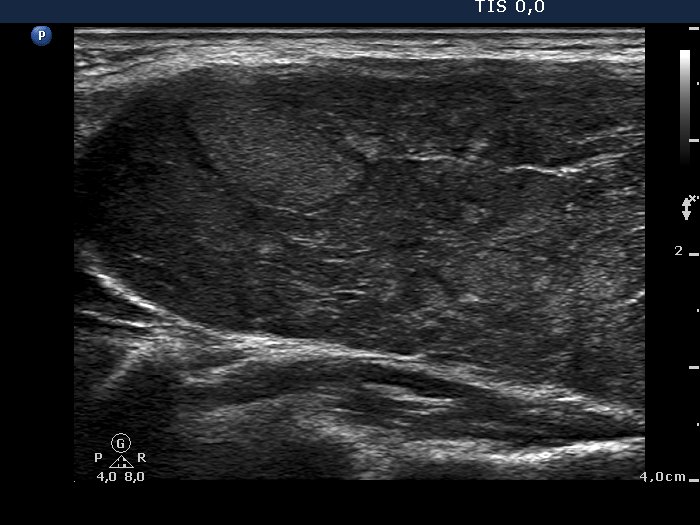

Case 974 (ultrasonographic picture 2)

Upper part of the right lobe, longitudinal scan. There are several smaller and one larger echonormal area within hypoechogenic background. Note fibrosis.